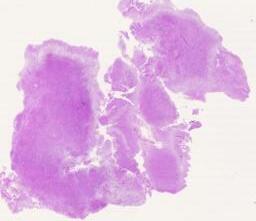

大体所见: 送检灰白色组织,共大约3.5 ×3.0 ×1.8cm,切面灰白色,质地中等。